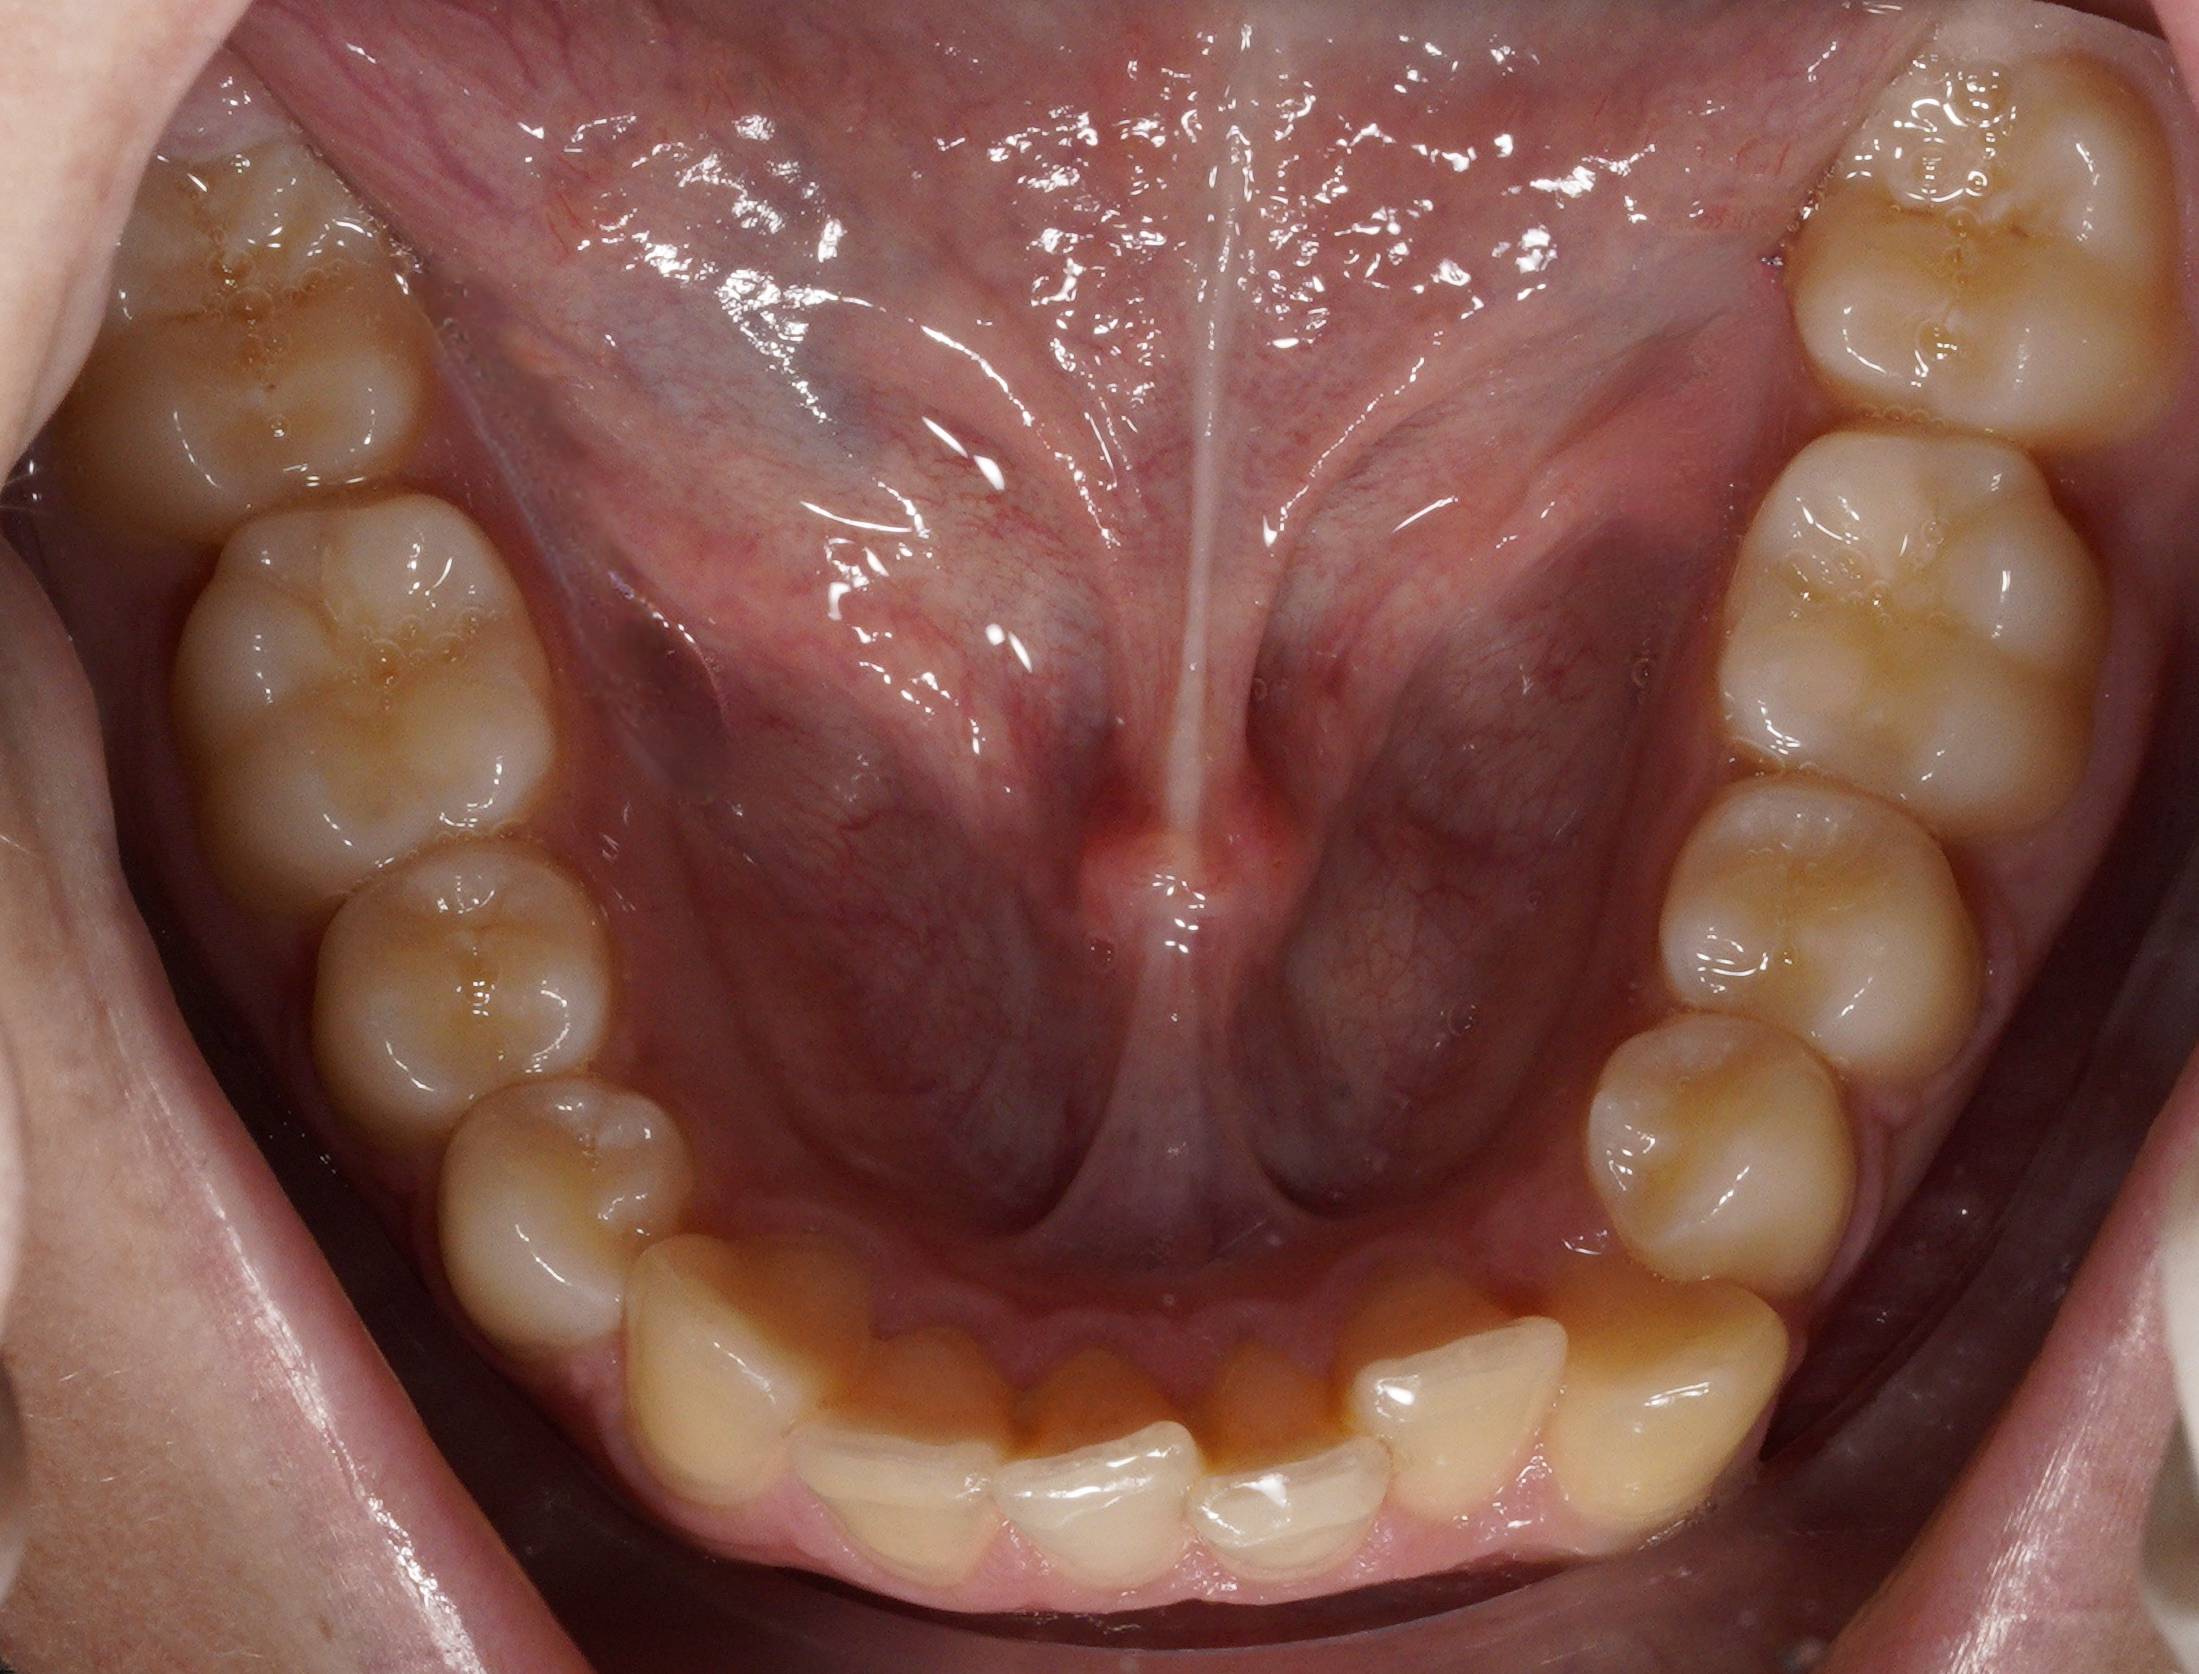

Un paziente di 14 anni si presenta lamentando insoddisfazione estetica del sorriso.

- Analisi Extra-orale: profilo convesso, asimmetria facciale e ridotta esposizione gengivale al sorriso.

- Analisi Intra-orale: II Classe molare e canina bilaterale, morso coperto (Deep Bite) e retro-inclinazione degli incisivi superiori (II Classe, Divisione 2). Persistenza di 53 e 63.

- Analisi Radiografica: inclusione bilaterale di 13 e 23 in Settore S5 (mesializzati rispetto alle radici dei laterali) con un angolo α di 76, 66°. La maturazione vertebrale (CS3-CS4) indica una fase post-picco o di fine crescita.

Caso clinico e diagnosi